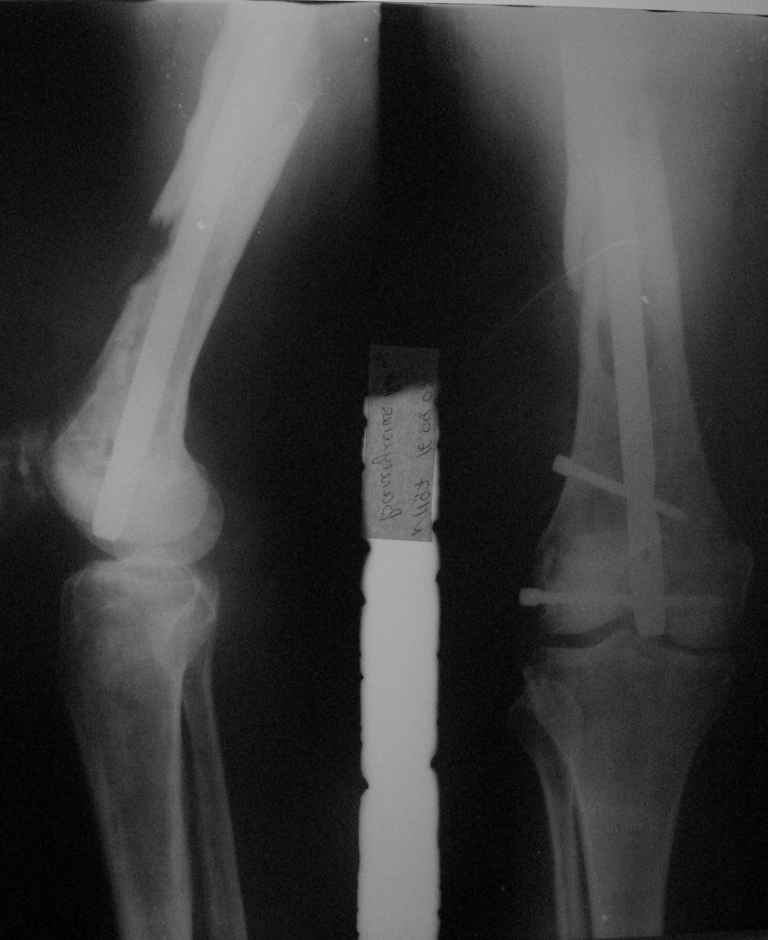

Реостеосинтез |  Сегодня |  |  |  | 1.5 года назад произведен синтез для улучшения качества жизни для по поводу патологического перелома на уровне открытой биопсии. Через 4 месяца открытый реостеосинтез с исправлением оси и восстановления опроспособности. В период после перелома лучевой и химиотерапии не получала. Месяц назад появилсь возрастающие боли в суставе. Ходит с тростью. Движения в коленном суставе качательные.На рентгеннограммах после реостеосинтеза намечалась тенденция к сращению. В области операционной раны периодически открывался-закрывался свищ. На последних - кроме миграции гвоздя в сустав - лизис костной мозоли. Можно ли одной из причин миграции считать длительную статическую фиксацию гвоздя? У кого-нибудь есть опыт на каких сроках проводить у онкобольных динамизацию? Что можно сделать для ликвидации боли и поддержания опороспособности конечности? Имеет ли смысл установка более толстого фиксатора без дистального блокирования? И вообще,ставить ли здесь вопрос о сохранении конечности?

МЮИ> последних - кроме миграции гвоздя в сустав - лизис костной мозоли.

При опухолях любая динамизация ведет к тому, что фрагменты телескопируются до упора винта в край овального отверстия, и он опять статический. Так что динамизация в услових увеличивающегося дефекта и не предполагается, гвоздь тут стопроцентный эндопротез. Так что проблемы здесь в том, что винты тонкие, которые если не ломаются, то режут разреженную кость. И выход - винтов вводить побольше, и потолще. Соответственно, гвоздь брать подходящий.

Он тут же двинется в колено по имеющемуся каналу. поэтому надо сделать нормальный блокируемый гвоздь, внизу винтов чтобы было больше 3, м диаметром больше 5 мм.

Саркомные переломы обычно не срастаются, по этому не зависимо от места метастаза фиксатор устанавливается максимально длинный и обязательно с блокировкой что бы сохранять длину кости даже после роста метастаза или при дополнительно метастазировании. В Вашем случае блокировочные гвозди выглядят тонкими и проведены только через один кортекс. Гвоздь толщиной более 10 мм с блокировочными шурупами 4-5 мм проведенные через обе кортикальные пластинки может обеспечить опороспособность даже если перелом не срастется или литический процесс распространится.

Посылаю первый снимок, который попался по руку.